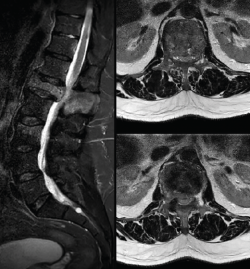

Se realiza una radiografía lumbosacra anteroposterior y lateral (Figura 1) en la que destaca un aplastamiento importante a nivel del cuerpo de L1.

Figura 1. Radiografía de columna dorsolumbar. Aplastamiento del cuerpo L1.